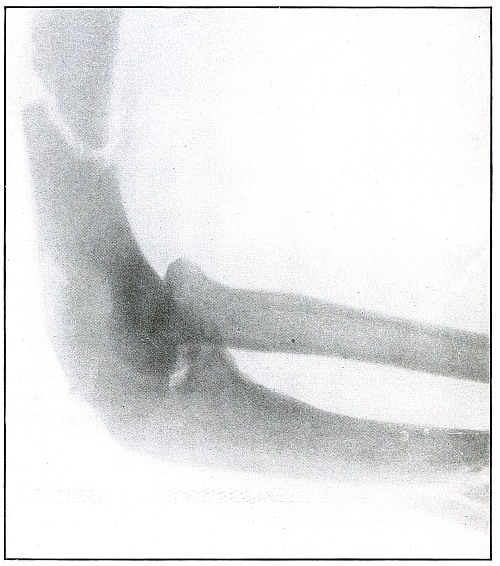

Rifle—Plate 18.

UPPER EXTREMITY.

Gunshot Fracture of the Elbow,

without Injury to the Great Vessels and Nerves.

Wound of entrance, posterior to the external condyle.

Wound of exit, large laceration in front and above the internal condyle.

The wound is an example of the misnamed “explosive” action of a rifle bullet. The force and direction of the missile, in high velocity, split the bone into many fragments, and, transmitting its energy to some of the fragments, carried them through the skin and caused the large laceration at the point of exit by the simultaneous escape of the bullet and fragments. The wound was so heavily infected, that a cellulitis advanced to the shoulder and to the wrist to such extent that the arm was marked by eminent surgical opinion for amputation. Free incision, drainage, antisepsis and incidental removal of detached fragments controlled the infection and brought about slow resolution. After six months of careful treatment the wound was healed with an ankylosed elbow with normal function of the forearm, except for limited rotation.

Treatment indicated in such cases is always conservative. Infections contraindicate any formal surgical interference. The dangers of infection in such cases are to be risked to avoid amputation.

Results may be considered favorable even with elbow ankylosis. [Pg 48]